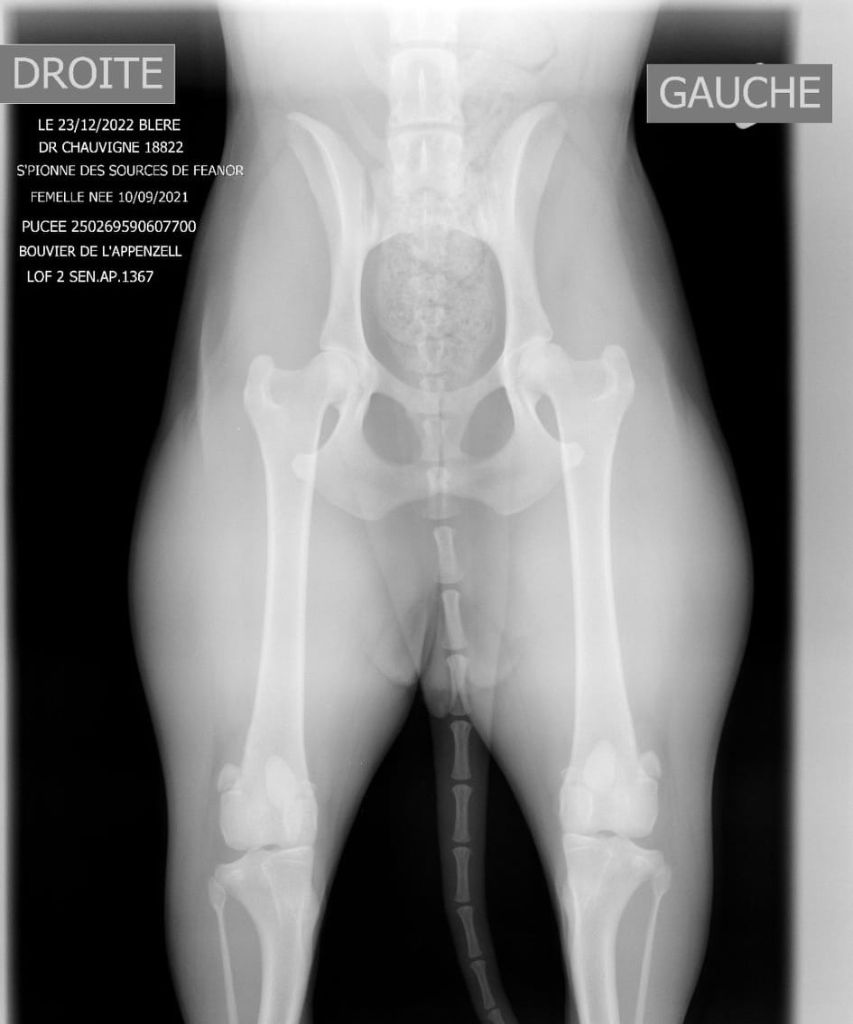

radio dysplasie hanches spionne

lecture officielle hanches s'pionne

ED : 00 HD : AA Patella : 00 |